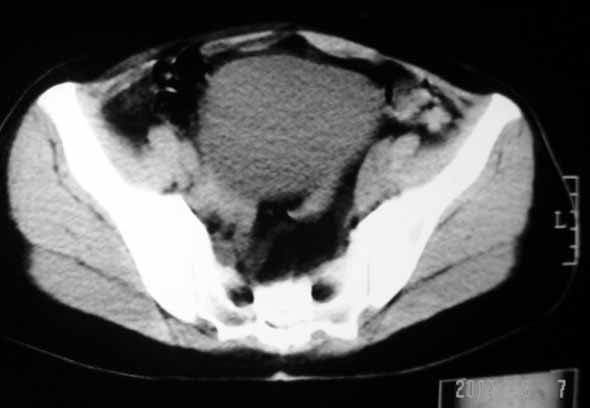

标题: CT8123:女46岁,左下腹胀痛不适1月,以前曾有月经过多史,现已 [打印本页]

标题: CT8123:女46岁,左下腹胀痛不适1月,以前曾有月经过多史,现已

子宫肌瘤,不强化不好说

考虑子宫们内膜癌并右侧腹股沟淋巴结转移

子宫增大密度较均匀,考虑子宫肌瘤,不强化不好说

考虑子宫肌瘤(变性)或子宫腺肌病,不排除内膜ca可能,不增强建议结合mri或b超检查。

子宫们内膜癌或子宫颈癌体部浸润并右侧腹股沟淋巴结转移

子宫增大密度较均匀,考虑子宫肌瘤可能性大,